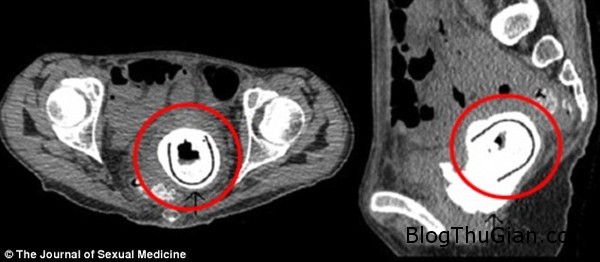

Hình chụp X-quang âm đạo của người phụ nữ.

Sau một loạt những triệu chứng như sút cân nghiêm trọng, rùng mình, hôn mê, thậm chí là hơi ham muốn tình dục, người phụ nữ đã tới bệnh viện để khám. Các kết quả kiểm tra cho thấy một dị vật kỳ lạ đang nhô ra từ bàng quang. Sau ca phẫu thuật, các bác sĩ đã lấy ra một món đồ chơi tình dục có chiều dài 11cm.

Được biết, người phụ nữ này mắc căn bệnh hiếm có tên thông bàng quang – âm đạo, một ống bất thường khiến nước tiểu chảy vào âm đạo. Ngoài ra, cô còn bị tắc đường tiết niệu. Sau khi gắp bỏ dị vật ra khỏi âm đạo cho nữ bệnh nhân này, các bác sĩ cũng tiến hành phẫu thuật chỉnh sửa dị tật âm đạo cho cô.